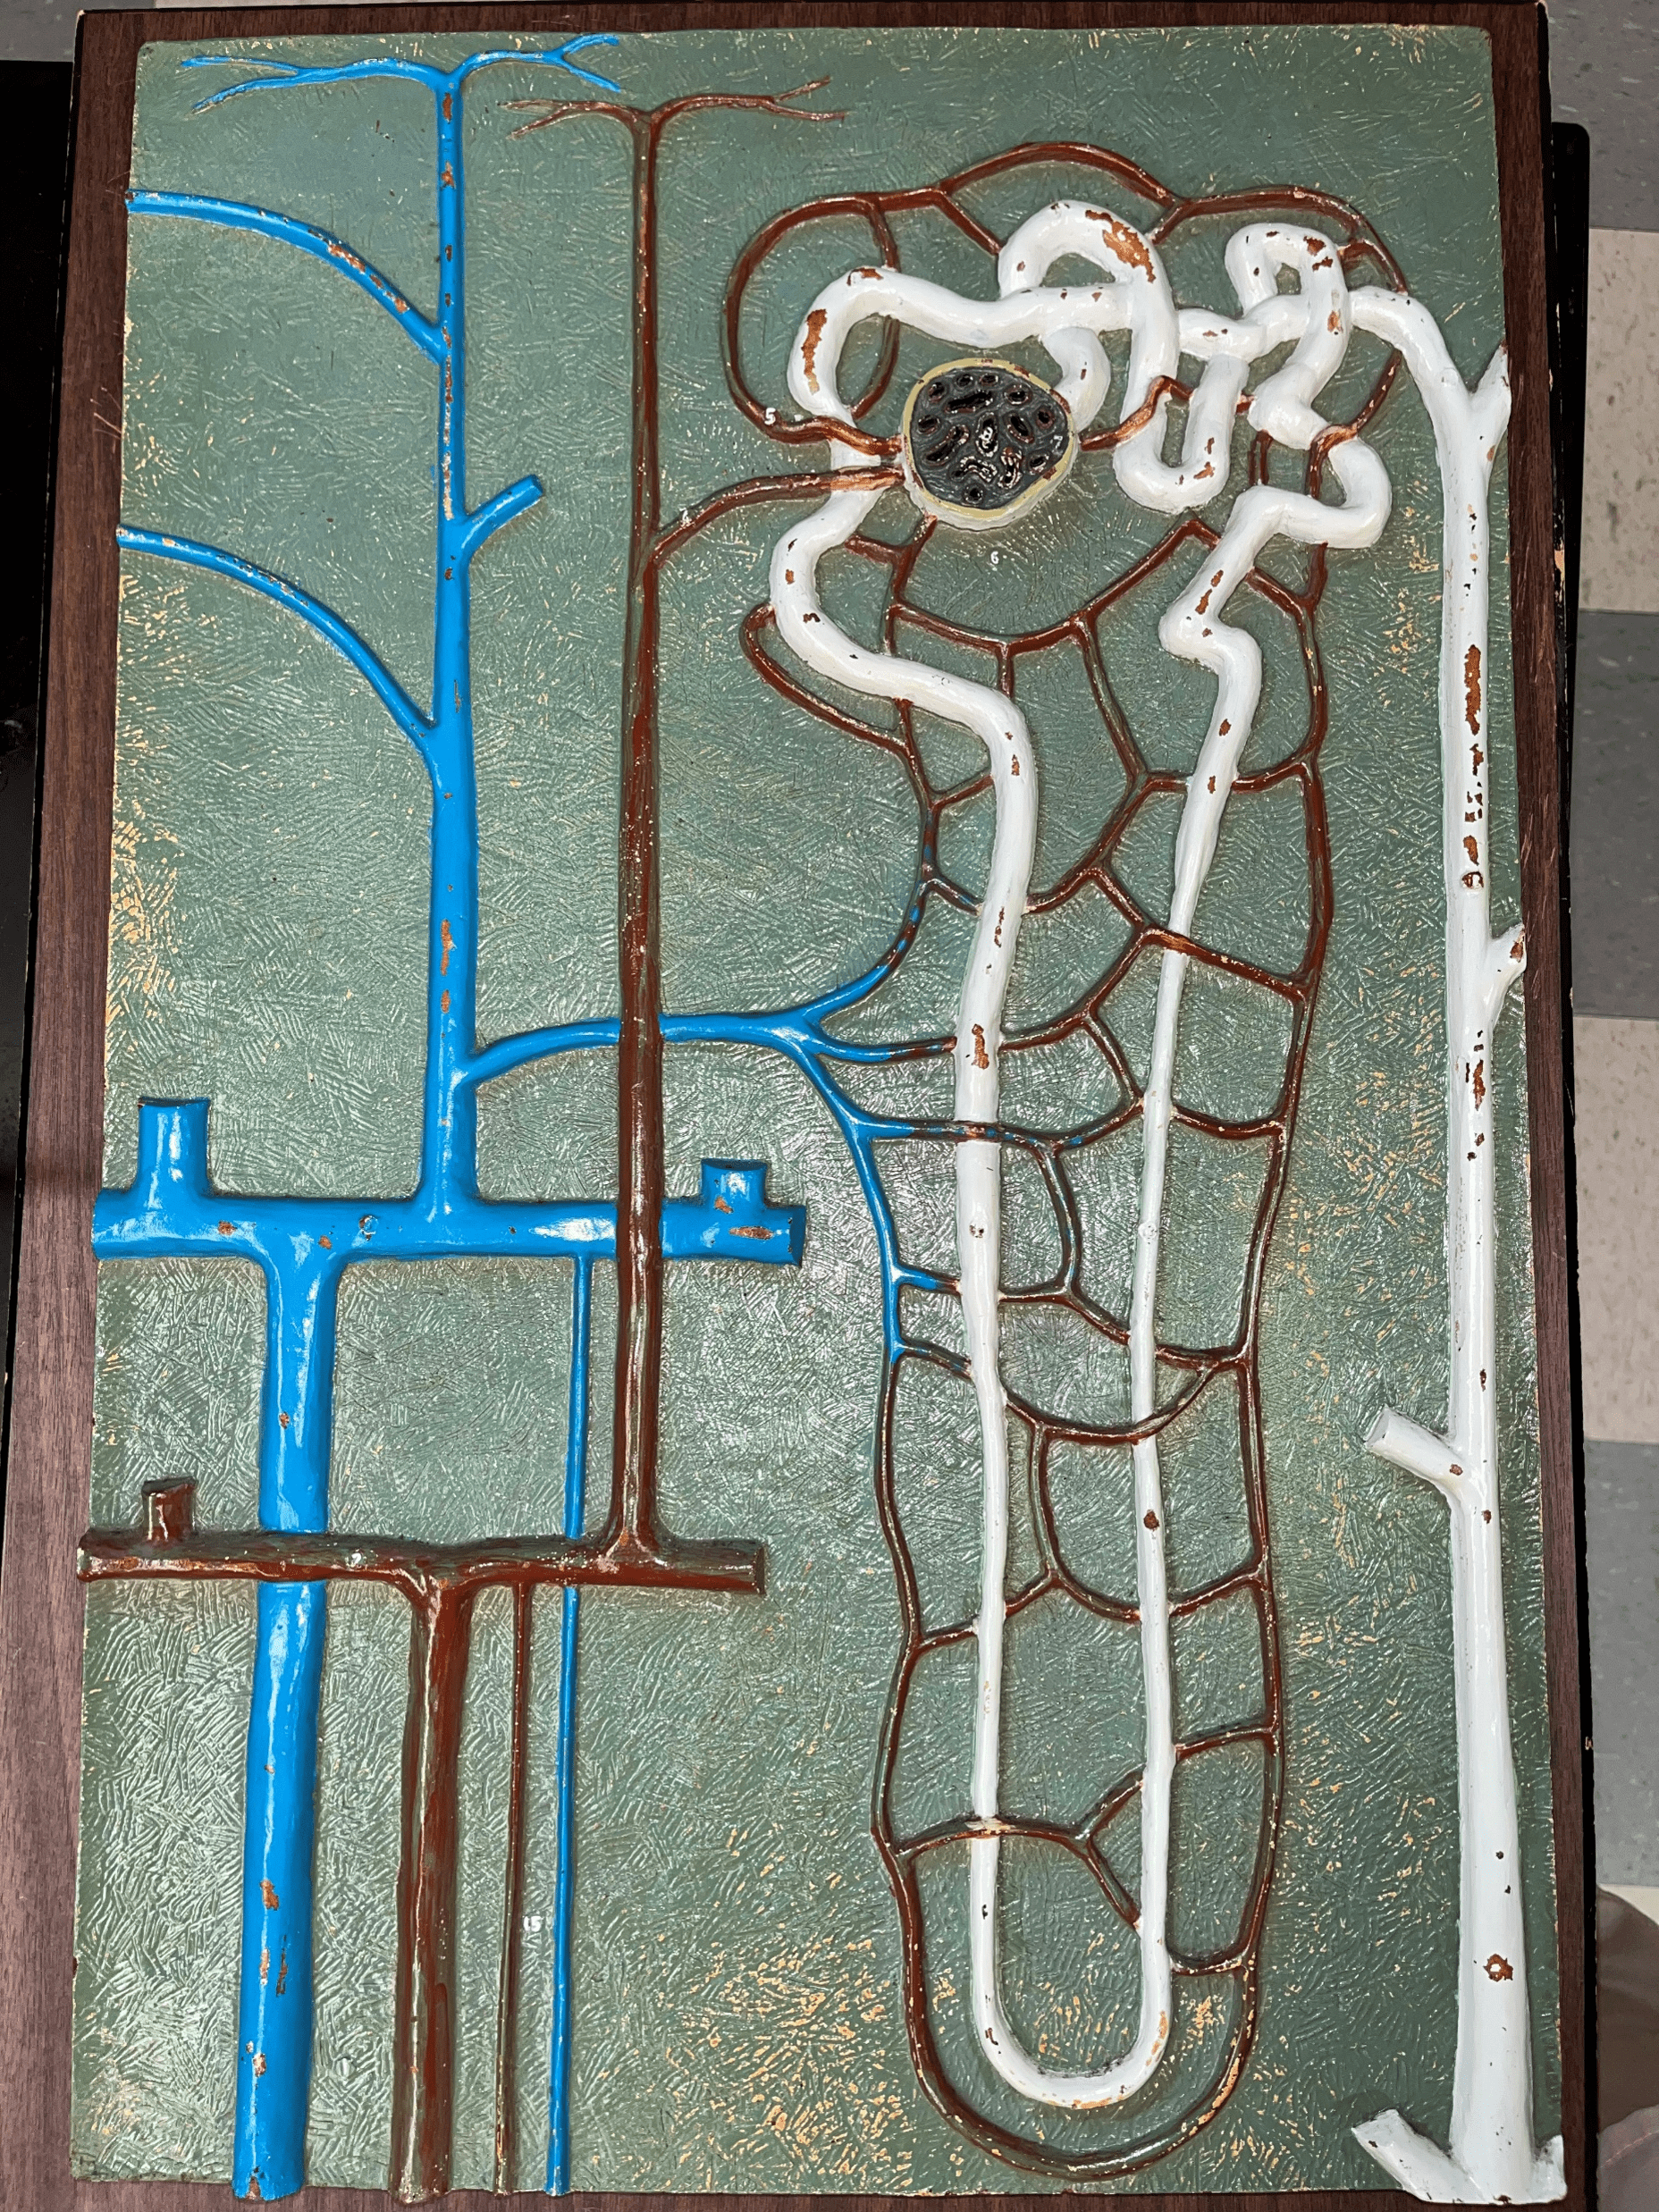

nephron

• The functional subunit of the kidney.

• Site of urine formation and renal function.

• Composed of a renal corpuscle and a renal tubule.

• Site of urine formation and renal function.

• Composed of a renal corpuscle and a renal tubule.

renal corpuscle

• Part of a nephron.

• Filters blood.

• Composed of a glomerulus enclosed within a glomerular capsule.

• Filters blood.

• Composed of a glomerulus enclosed within a glomerular capsule.

glomerulus

• Slide histology of the nephron.

• Part of a renal corpuscle.

• The capillary network of a renal corpuscle.

• Part of a renal corpuscle.

• The capillary network of a renal corpuscle.

capsular space

• Slide histology of the nephron.

• Part of a renal corpuscle.

• The interior of the glomerular capsule.

• Part of a renal corpuscle.

• The interior of the glomerular capsule.

glomerular capsule

• Slide histology of the nephron.

• Part of a renal corpuscle.

• A wall enclosing the glomerulus.

• Shown in the image is the parietal layer.

• Part of a renal corpuscle.

• A wall enclosing the glomerulus.

• Shown in the image is the parietal layer.

renal tubule

• Slide histology of the nephron.

• Part of a nephron.

• Modifies glomerular filtrate by reabsorption and secretion of water and ions.

• Divided into the proximal convoluted tubule, loop of Henle, and distal convoluted tubule.

• Part of a nephron.

• Modifies glomerular filtrate by reabsorption and secretion of water and ions.

• Divided into the proximal convoluted tubule, loop of Henle, and distal convoluted tubule.

proximal convoluted tubule

• The first part of a renal tubule.

• Primary site of water and solute reabsorption.

• Begins immediately after the renal corpuscle.

• Abbreviated PCT.

• Primary site of water and solute reabsorption.

• Begins immediately after the renal corpuscle.

• Abbreviated PCT.

descending limb

• The proximal second part of a renal tubule.

• Part of the loop of Henle.

• Permeable to water but not solutes.

• Part of the loop of Henle.

• Permeable to water but not solutes.

ascending limb

• The distal second part of a renal tubule.

• Part of the loop of Henle.

• Permeable to solutes but not water.

• Part of the loop of Henle.

• Permeable to solutes but not water.

distal convoluted tubule

• The third part of a renal tubule.

• Primary site of secretion of excess solutes.

• Abbreviated DCT.

• Primary site of secretion of excess solutes.

• Abbreviated DCT.

collecting duct

• The convergence of several distal convoluted tubules.

• Descends through the renal pyramid.

• Merges with others to form larger papillary ducts that drain into the minor calyces.

• Abbreviated CD.

• Descends through the renal pyramid.

• Merges with others to form larger papillary ducts that drain into the minor calyces.

• Abbreviated CD.

afferent arteriole

• Branches of an interlobular artery.

• Supplies the glomerulus of a nephron for blood filtration.

• Supplies the glomerulus of a nephron for blood filtration.

efferent arteriole

Vessel carrying blood away from the glomerulus to the peritubular capillaries.

peritubular capillaries

• Branches of an efferent arteriole.

• Supplies the adjacent renal tubules in the renal cortex.

• Supplies the adjacent renal tubules in the renal cortex.

vasa recta

• Branches of an efferent arteriole.

• Supplies the loops of Henle in the renal medulla.

• Supplies the loops of Henle in the renal medulla.